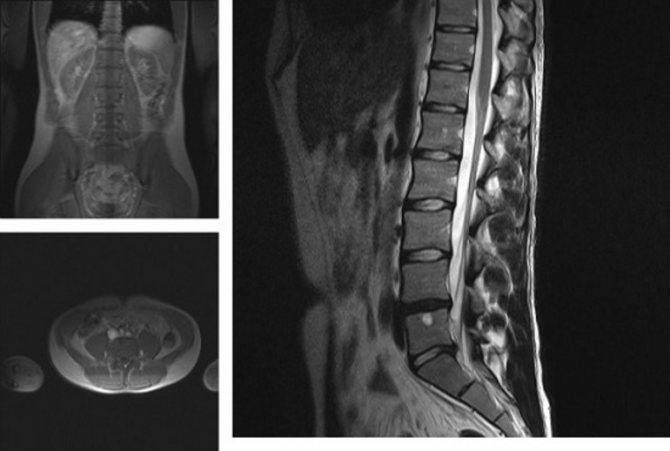

Диагностировать патологии можно с помощью разных методов: рентгена, МРТ, КТ

С помощью МРТ можно оценить дегенеративные процессы фасеточных суставов.

Заключение «спондилоартроз» медики выносят на основании данных болезни, конкретных жалоб пациента и изучения с помощью пальпации. К инструментальным способам постановки диагноза относят:

- Рентгенография. На полученом снимке сложнее определить заболевание мелких суставов позвоночника, нежели разрушение больших суставов.

- Компьютерная томография. Данный способ послойного изучения хрящевых тканей осуществляется с помощью задавания дистанции между срезами. Для изучения суставов надо установить наименьшую дистанцию. Так можно увидеть присутствие остеофитов и краевого остеосклероза. Непосредственно по сведениям полученным в результате данного способа у больных замечают дегенеративно-дистрофические изменения поясничного отдела, выявляют признаки остеохондроза. На обследовании МР видно грыжи дисков L4-S1. Область структурных изменений на уровне тела L4 позвонка слева свидетельствует о секвестрированном грыжевом фрагменте. По итогам заключения — грыжи дисков L3-L5 величиной 0,5-0,7 см означают развитие спондилоартроза.